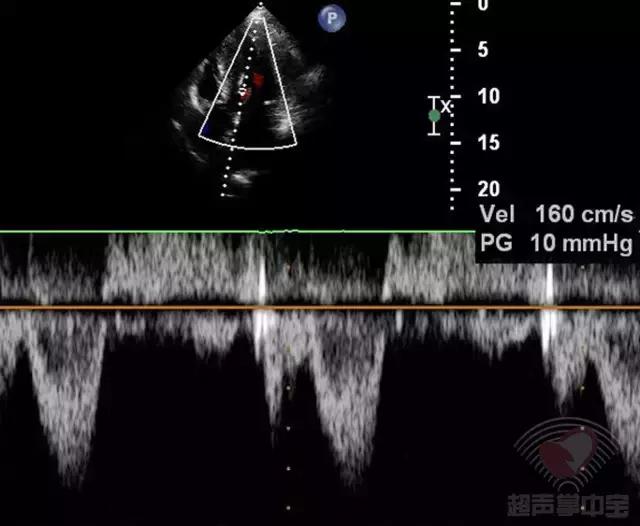

经皮经腔间隔心肌消融术后半年门诊随访,患者劳力型呼吸困难明显改善,未发生晕厥,复查超声心动图(图4):左室流出道最大瞬时流速和压差为:160cm/s,PG:10mmHg。

图4 非对称性肥厚型梗阻性心肌病:经皮经腔间隔心肌消融术后6个月复查超声心动图心尖五腔心切面CW测左室流出道峰值流速160cm/s